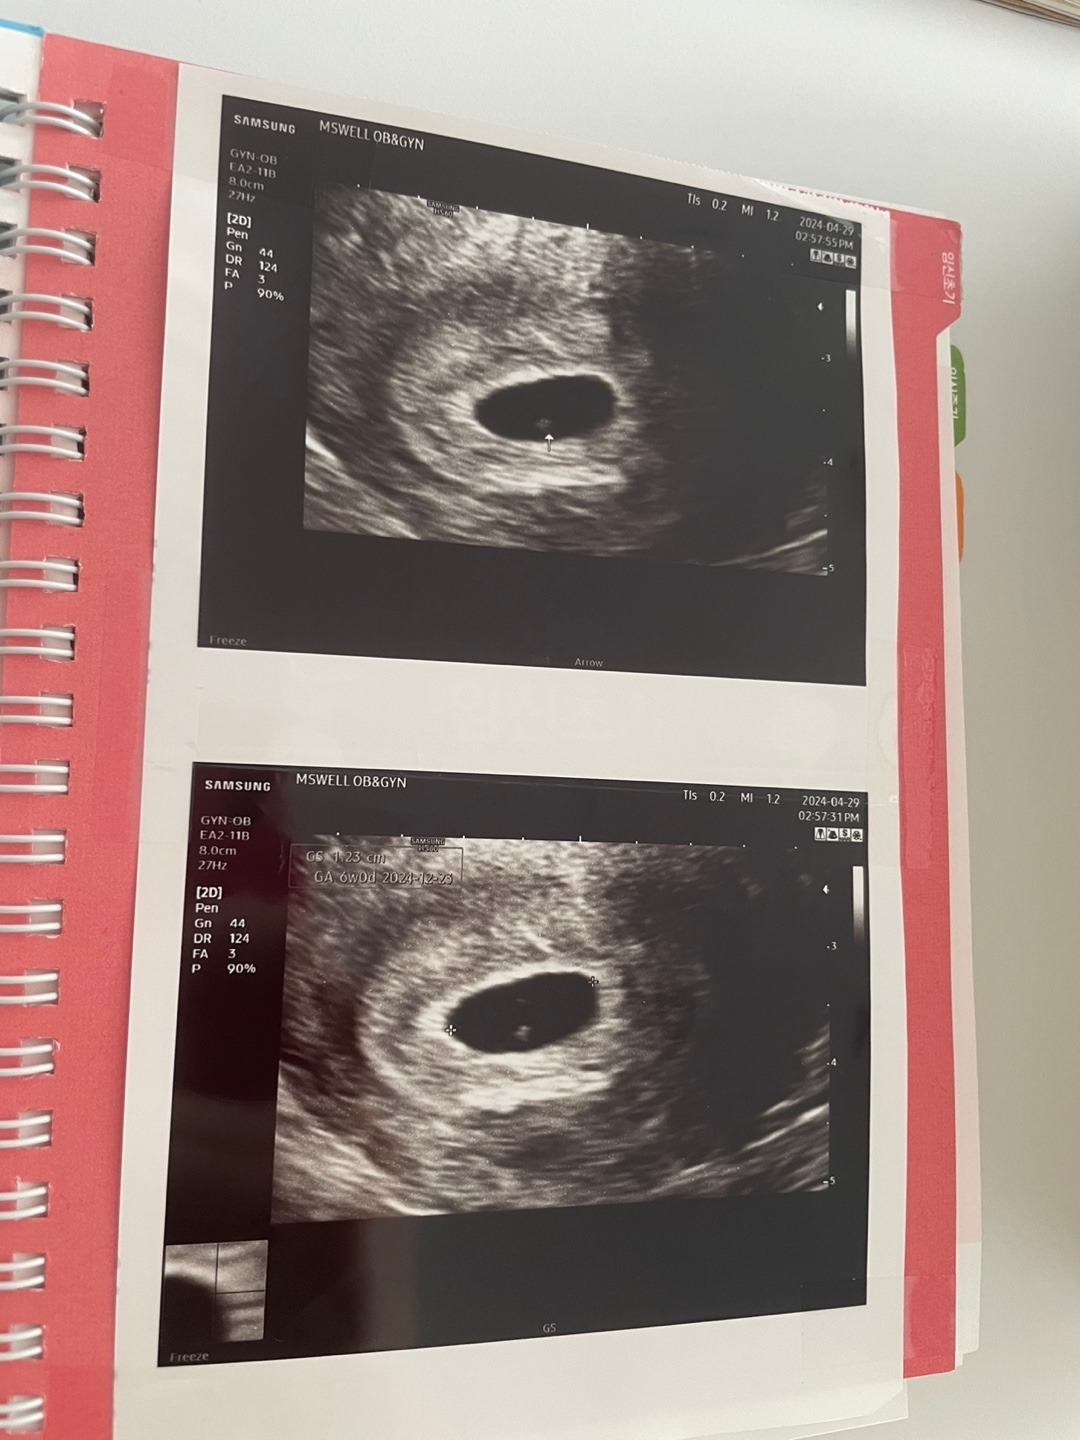

어두운 화면에 아기집이 보였다. 다행이다 싶으면서도 큰 감흥이 일지는 않았다. 오히려 의사 선생님이 나보다 더 기뻐하셨다. 유일하게 비밀을 아는 한 사람. 가족 말고 아기가 무사하기를 바라는 이가 있음에 감사했다. 기쁜 내색 없는 내가 마음 쓰이셨던 걸까. 연신 괜찮을 거라며 걱정말라셨다.

진단명은 절박유산.